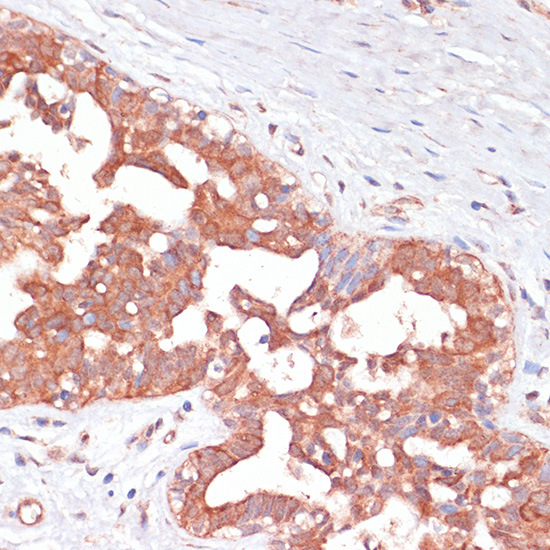

Immunohistochemistry of paraffin-embedded Human mammary cancer using PGD antibody.